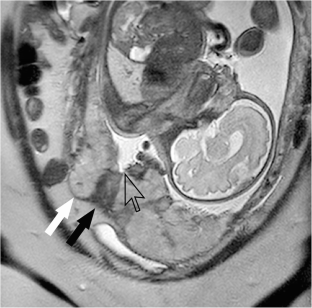

Fig. 1

Fig. 2

Fig. 3

Fig. 4

Fig. 5

Fig. 6

Fig. 7

Fig. 8

Fig. 9

Fig. 10

Fig. 11

Fig. 12